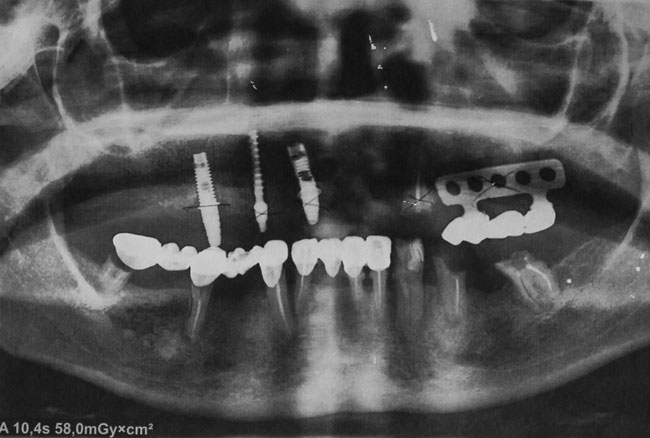

The period of operation of the construction lasted 13 years, after what the bridges that stood on the implants and natural teeth on the maxilla were broken down. In 2013 the plate implant was removed and a fracture of the body of implants 1.3; 1.1, 1.5 and abutments were diagnosed. Available endosseous implant part 1.5 is stable, immobile, with no signs of inflammation of the surrounding bone and mucosa (see Fig. 3)

Taking into account the negative experience of the removable dentures laminar use, there was recommended to install two-stage implants in the upper jaw in area of the missing 1.6; 1.3; 1.2; 2.1; 2.3; 2.5 teeth with the inclusion of a prosthetic construction a cylindrical implant which was set 15 years ago.